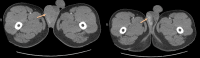

Figure 3. A pelvic CT (transverse view) revealing a heterogeneous enlarged right testes with central foci of hypodensity.